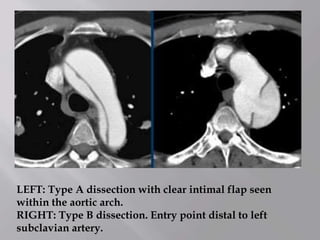

LEFT: Type A dissection with clear intimal flap seen

within the aortic arch.

RIGHT: Type B dissection. Entry point distal to left

subclavian artery.